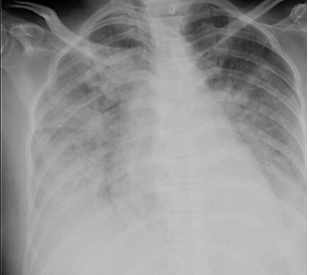

Paciente recebeu as condutas adequadas. No 4° dia de internação, paciente apresentou quadro de dispneia importante, associado à palidez cutânea e taquidispneia. Ao Exame físico, regular estado geral, hidratado, corado, acianótico, afebril. Murmúrio vesicular presente com crepitações até ápice, Bulhas rítmicas normofonéticas, com sopro sistólico 2+/6+ em ápice; Pressão arterial de 110/60 mmHg. Saturação de oxigênio de 86%; Pele fria. Realizou a radiografia de tórax abaixo: